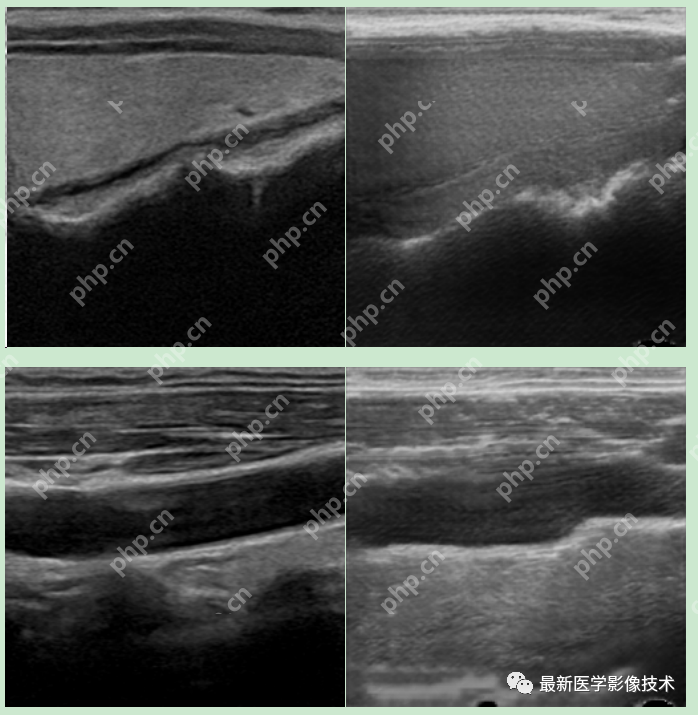

5、验证集部分生成结果

左图为低质量图像,中间为生成的高质量图像,右图为真实的高质量图像。